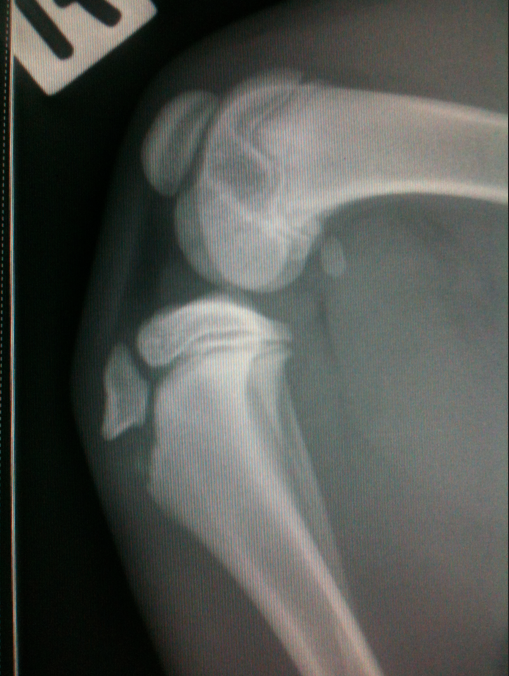

Please look below at all these x-rays from last years random friend’s injuries ( and these are without even searching as these happen all the time). If it is not a growth plate , it is a neck, back, wrist, hock, ribs or any large bones for that matter. One of the most common example is when a small piece of the knee joint splits, which end up in a 2-3000€ surgery. I do not see much point in taking such a huge risk, so don’t run adults and pups! Period!

Here is the proof! More info after the pictures!

• Type 3 – elbow (distal humerus)

• Type 4 – elbow (distal humerus)